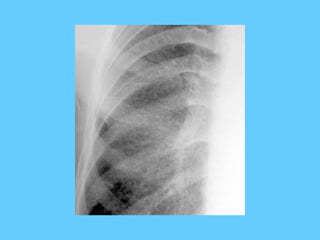

Chronic tuberculosis